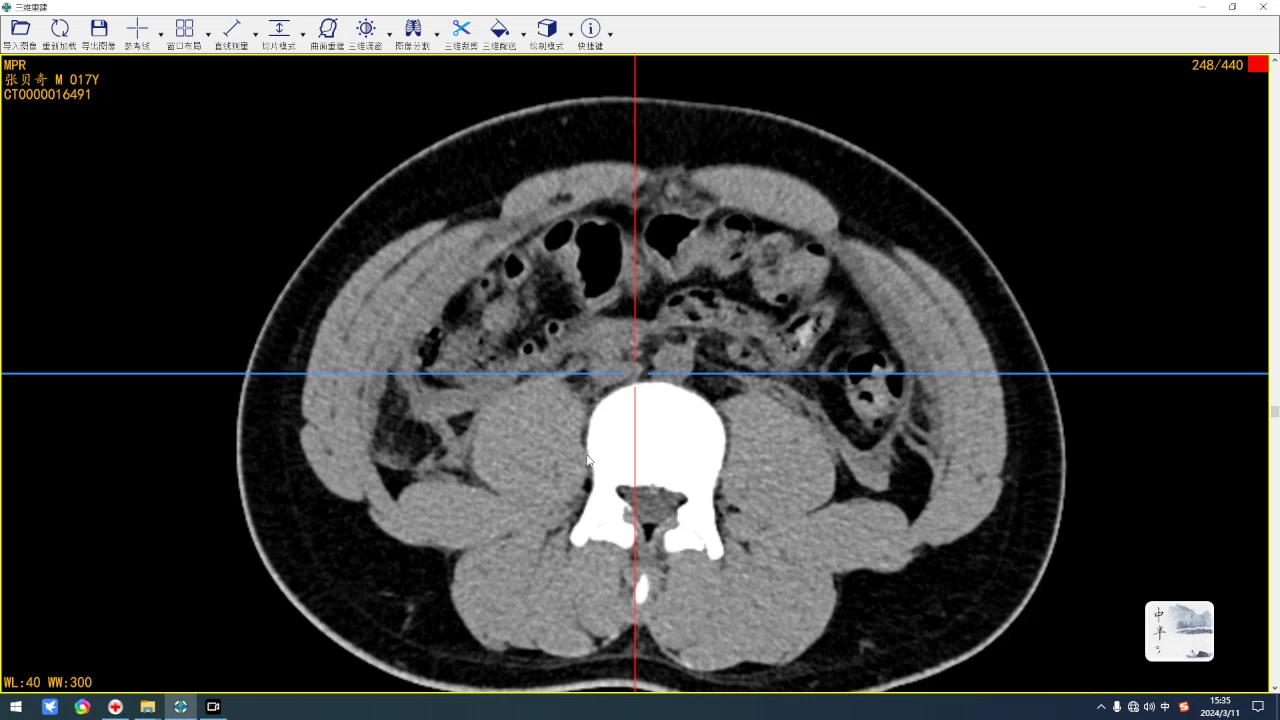

简要病史:右侧耻骨下肢骨折及右手掌骨骨折来来诊。

全腹部是刚入院第二天的检查,盆腔是入院检查。

下午复查的后,脐区腹直肌后方的包块比早上有缩小,这会不会是一种疝?